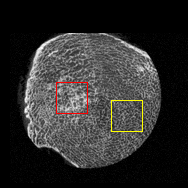

Figure 4: Visual comparsion of SRCT Case 111 from the Tibia dataset. The restored bony structures are shown in the red and yellow boxes in Fig. 5. The display window is [-900, 2000] HU.

Figure 5: Zoomed regions of interest (ROIs) marked by the red rectangle in Fig. 4. The restored image with GAN-CIRCLE reveals subtle structures better than the other variations of the proposed neural network, especially in the marked regions. The display window is [-900, 2000] HU.

III-D Experimental Results with the Tibia Dataset

We evaluated the proposed algorithms against the state-of-the-art algorithms on the tibia dataset. We present typical results in Fig. 4. It is observed that BM3D can effectively remove the noise, but it over-smoothens the noisy LR images. Then, the interpolation-based methods (NN+, Bilinear+, Bicubic+, Lanczos+) yield noticeable artifacts caused by partial aliasing. On the other hand, the DL-based methods suppress such artifacts effectively. It can be seen that our proposed GAN-CIRCLE recovers more fine subtle details and captures more anatomical information in Fig. 5. It is worth mentioning that Fig. 4 shows that there are severe distortions of the original images but SRGAN generates compelling results in Figs. 6-8, which indicate VGG network is a task-specific network which can generate images with excellent image quality. We argue that the possible reason is that the VGG network [68] is a pre-trained CNN-based network based on natural images with structural characteristic correlated with the content of medical images [80]. Fig. 5 presents that the proposed GAN-CIRCLEs can predict images with shaper boundaries and richer textures than GAN-CIRCLE, and GAN-CIRCLEu which learns additional anatomical information from the unpaired samples. The quantitative results are in Table II. The results demonstrate that the G-Forward achieves the highest scores using the evaluation metrics, PSNR and SSIM, which outperforms all other methods. However, it has been pointed out in [81, 82] that high PSNR and SSIM values cannot guarantee a visually favorable result. Non-GAN based methods (FSRCNN, ESPCN, LapSRN) may fail to recover some fine structure for diagnostic evaluation, such as shown by zoomed boxes in Fig. 5. Quantitatively, GAN-CIRCLE achieves the second best values in terms of SSIM and IFC. It has been pointed out in [83] that IFC value is correlated well with the human perception of SR images. Our GAN-CIRCLEs obtained comparable results qualitatively and quantitatively. Table II shows that the proposed semi-supervised method performs similarly compared to the fully supervised methods on the tibia dataset. In general, our proposed GAN-CIRCLE can generate more pleasant results with sharper image contents.